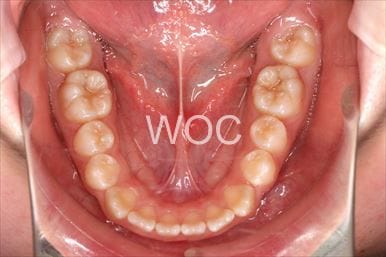

治療前1

-

治療前2

-

治療前3

-

治療前4

-

治療前5

- 年齢:24歳女性

- 主訴:上下前歯のガタガタが気になる

- 基本矯正料金:80万円

- 治療期間:1年5ヶ月

- 非抜歯